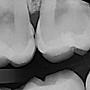

齒縫間蛀牙

[ teeth_salon ]3 留言, 推噓總分: 0

作者: jrt7c8 - 發表於 2018/12/07 05:56(7年前)